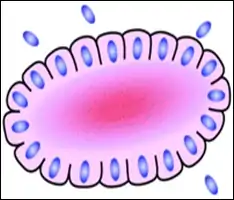

A rosette is a cell formation in a halo or spoke-and-wheel arrangement, surrounding a central core or hub. The central hub may consist of an empty-appearing lumen or a space filled with cytoplasmic processes. The cytoplasm of each of the cells in the rosette is often wedge-shaped with the apex directed toward the central core: the nuclei of the cells participating in the rosette are peripherally positioned and form a ring or halo around the hub.[2]

Loss or gain of genetic information is the main cause of rosette and pseudorosette formation. The cell populations exhibiting neuronal differentiation are believed to secrete surface glycoproteins and glycolipids which mediate cell-to-cell recognition and adhesion. One hypothesis is that these sticky cell surface markers cause the developing cell bodies to cluster or aggregate and their primitive neurites to tangle. As the cells grow, the neurite tangle remains centrally located and the cell bodies are squeezed to the periphery, thus explaining the rosette pattern. Depending upon their location, ependymal cells may display 2 cell poles. A luminal pole projects to the ependymal lining of a ventricle and a “submesenchymal pole” projects toward the surface of the brain demonstrating glial processes and peripherally situated footplates. Frieda and Pollak conceptualize the architecture of ependymomas as a primitive neural tube turned inside out with the submesenchymal poles converging toward a central vessel, thus forming a pseudorosette rather than projecting centrifugally toward the pia.[2]

Unlike the center of the Homer Wright rosette, the central lumen is devoid of fiber-rich neuropil. The defining feature of this rosette is central extension of cytoplasmic projections of the surrounding cells. Like the Homer Wright rosette, the Flexner–Wintersteiner rosette represents a specific form of tumor differentiation.[5][6][7][8] Electron microscopy reveals that the tumor cells forming the Flexner–Wintersteiner rosette have ultrastructural features of primitive photoreceptor cells.[9] Furthermore, the rosette lumen shows similar staining patterns as in rods and cones,[10] suggesting that Flexner–Wintersteiner rosettes represent a specific form of retinal differentiation. In addition to being a characteristic finding in retinoblastomas, Flexner–Wintersteiner rosettes may also be found in pinealoblastomas and medulloepitheliomas.[5]

Structure of a Flexner–Wintersteiner rosette

Structure of a Flexner–Wintersteiner rosette